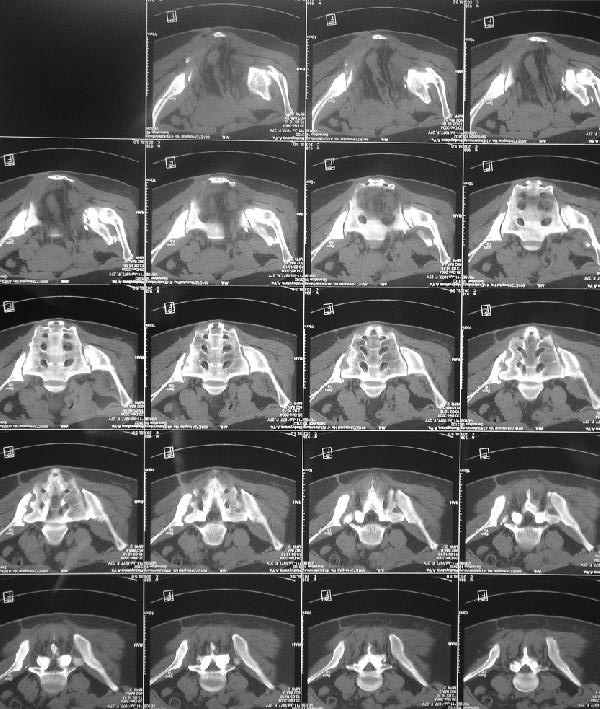

Снимки до лечения: